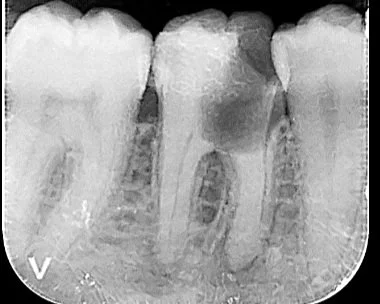

Severe decay. Tooth in 2 parts. Possible to save via hemisection.